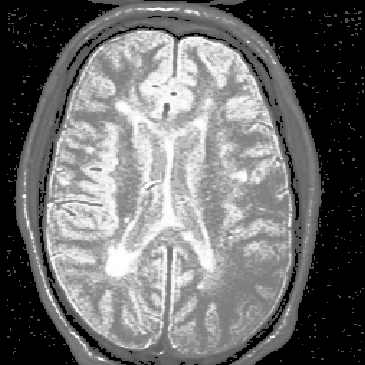

MR images contain unwanted intensity variation due to inhomogeneity in the ``uniform'' magnetic field, , inhomogeneity in the applied RF pulse sequence, , nonuniformity in RF field coil(s) used to measure the FID response signal, and nonuniform loading of the coils by the patient [41][5]. The overall intensity variation, referred to as RF inhomogeneity, is illustrated in Figure 2.4.

Figure 2.4: An axial MR slice exhibiting intensity variation due to RF inhomogeneity. Notice that the image intensity drops in the lower right corner.